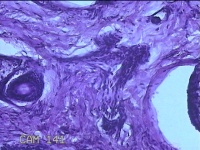

性别

男

年龄

23岁

临床诊断

右耳部肿物

一般病史

右耳前无痛性肿物20余年。

标本名称

大体所见

灰白暗红色肿物0.7x1.5x0.2cm一个,表面糜烂。